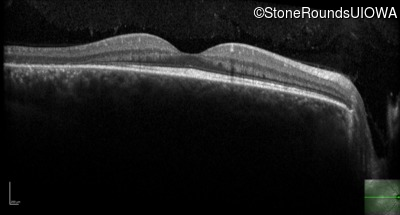

Age at visit: 26 years

OD OS